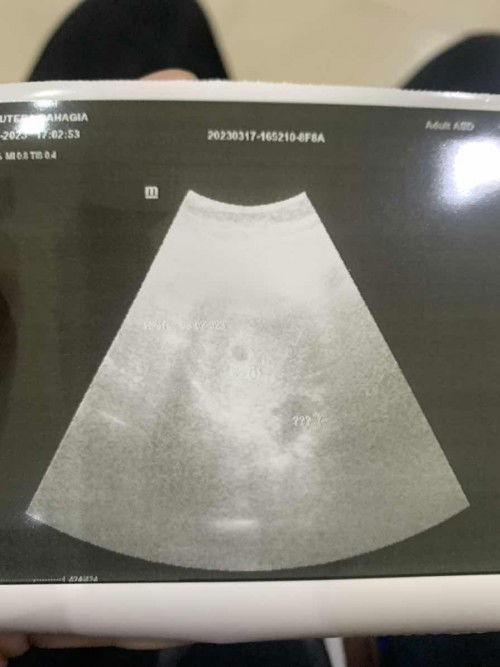

itu kayaknya ada 2 bulatan ya bund. Yg atas dan kanan bawah yg dikasih tanda ??? itu USG 2D atau Transvaginal? menurut HPHT sudah brp week bund? coba USG ditempat lain juga bund, mungkin dokternya bisa kasih penjelasan yg lebih jelas.

Baca lagisepertinya sudah ada kantongnya ya bunda? kayaknya juga sudah ada calon janinnya. semoga tebakannya benar 🤭

itu udah ada kantungnya bun.. brp minggu itu kandungannya

itu kyknya masih ragu itu apa makanya dikasih tanda tanya

Iyabun bener aku nanya katanya kyk sel telur tp wajar krn proses pembuahan jd menebal tp aku kurang yakin krn dia ngasi ??? di usg wkwk